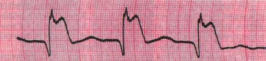

1) Оцените представленную ЭКГ.

1) На представленной ЭКГ желудочковая экстрасистолия, об этом свидетельствуют измененный комплекс QRS, интервал ТР, изменение в продолжительности цикла RR.